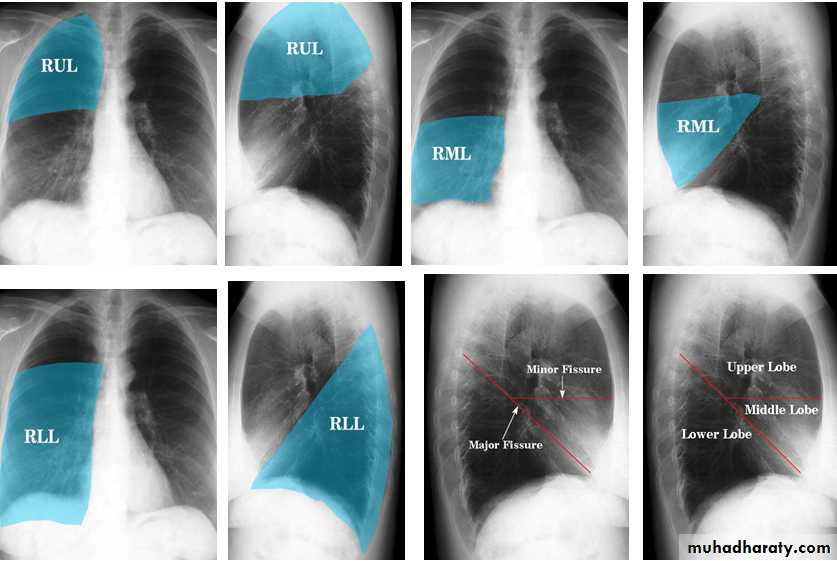

The lung

The left lung has two lobes and the right has three

Each lobe has its own pleural covering

The horizontal fissure (right) is often seen on a normal frontal view

The oblique fissures are often seen on a normal lateral view .

Lobes and fissures

This cut-out of a lateral chest x-ray shows the positions of the lobes of the right lung

On the left the oblique fissure is in a similar position but there is usually no horizontal fissure, and so there are only two lobes on the left.

Radiologic anatomy of the RT lung lobes

Radiologic anatomy of the LT lung lobes